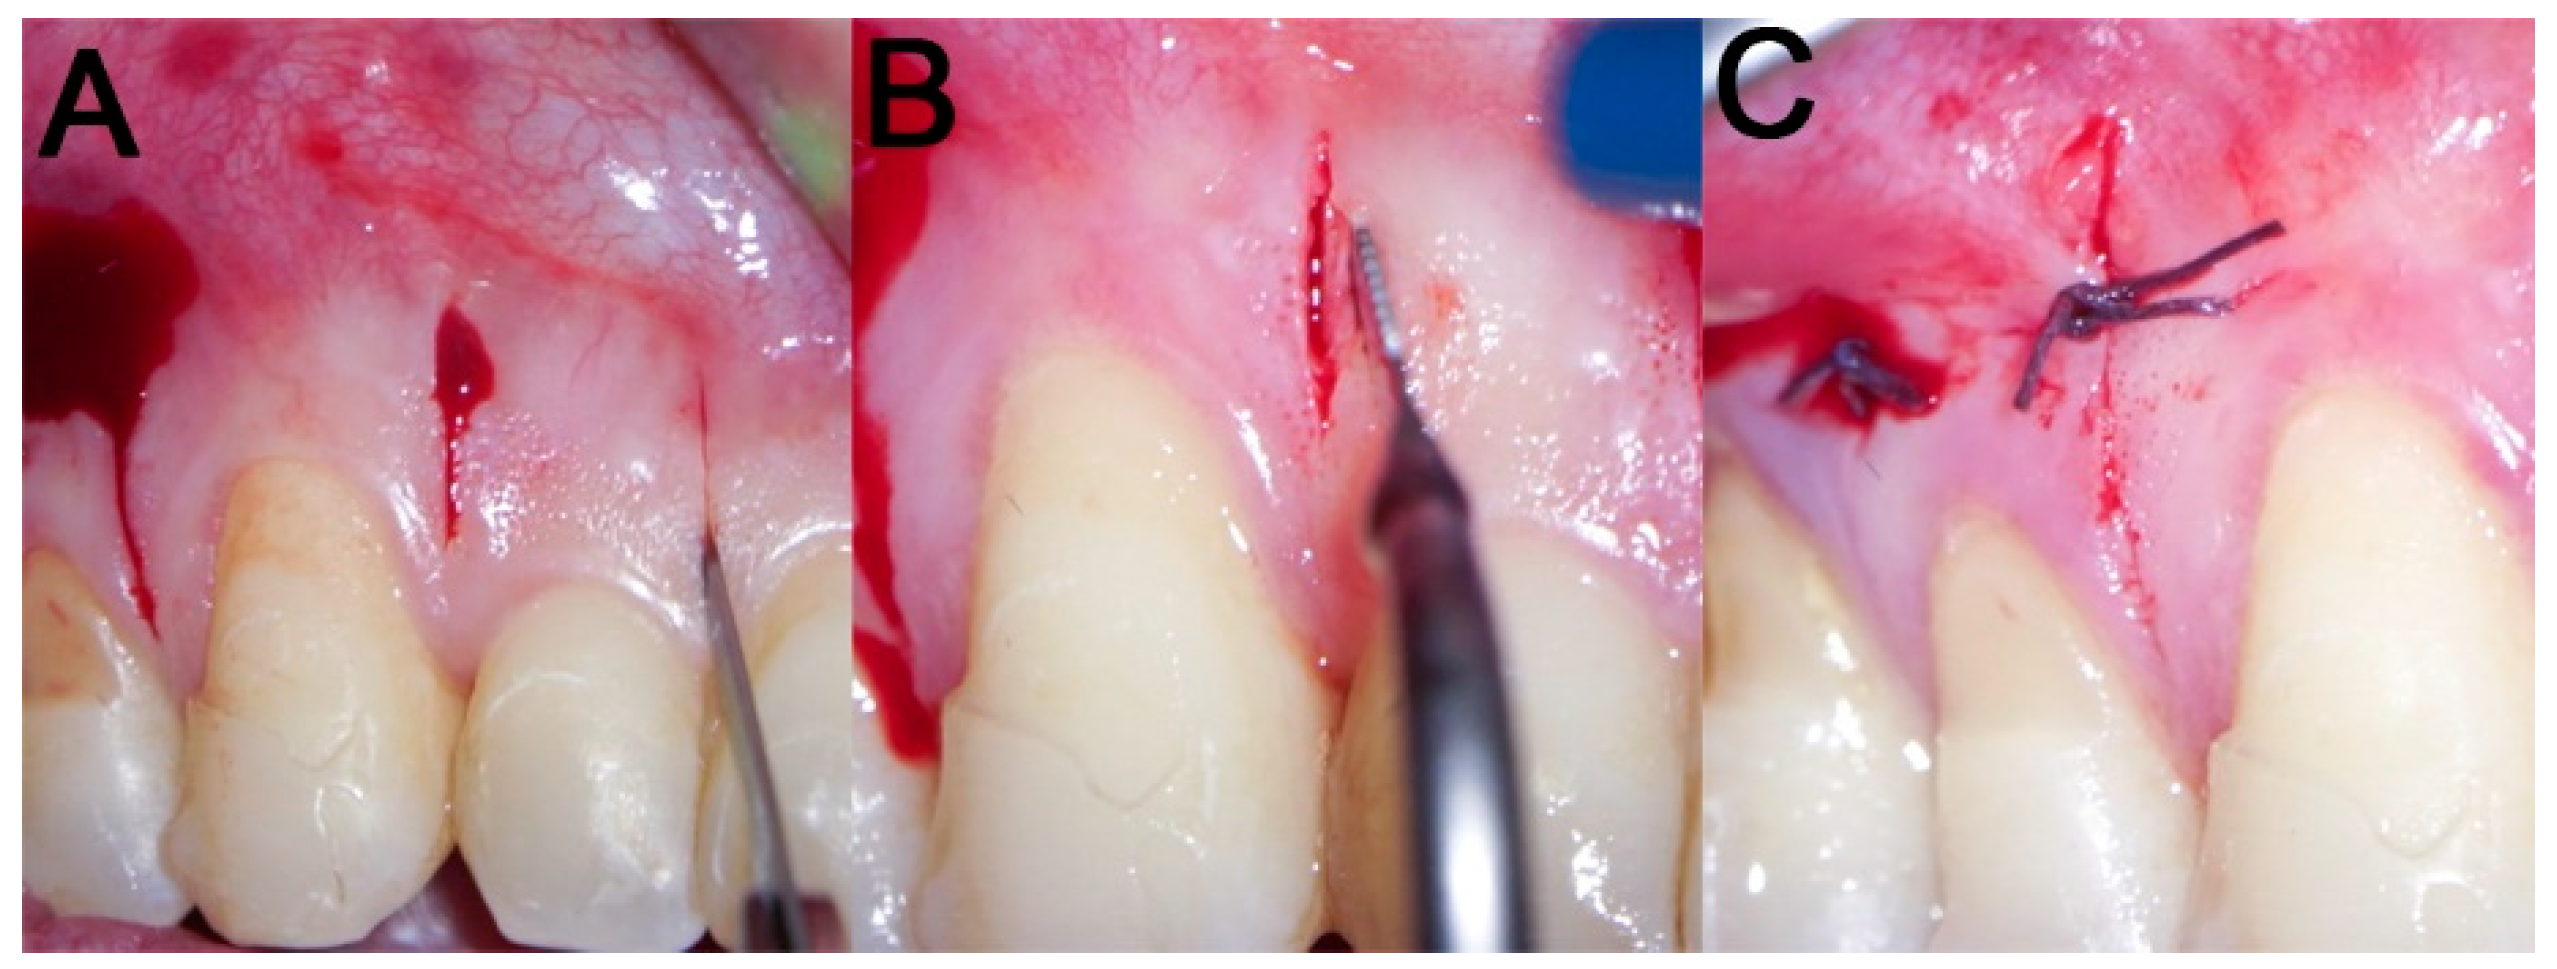

2.3. Surgical Procedure

2.3.1. Example—Anterior Open-bite